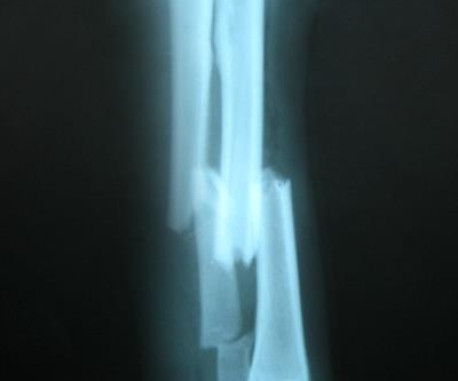

Bilgisayarlı Röntgen